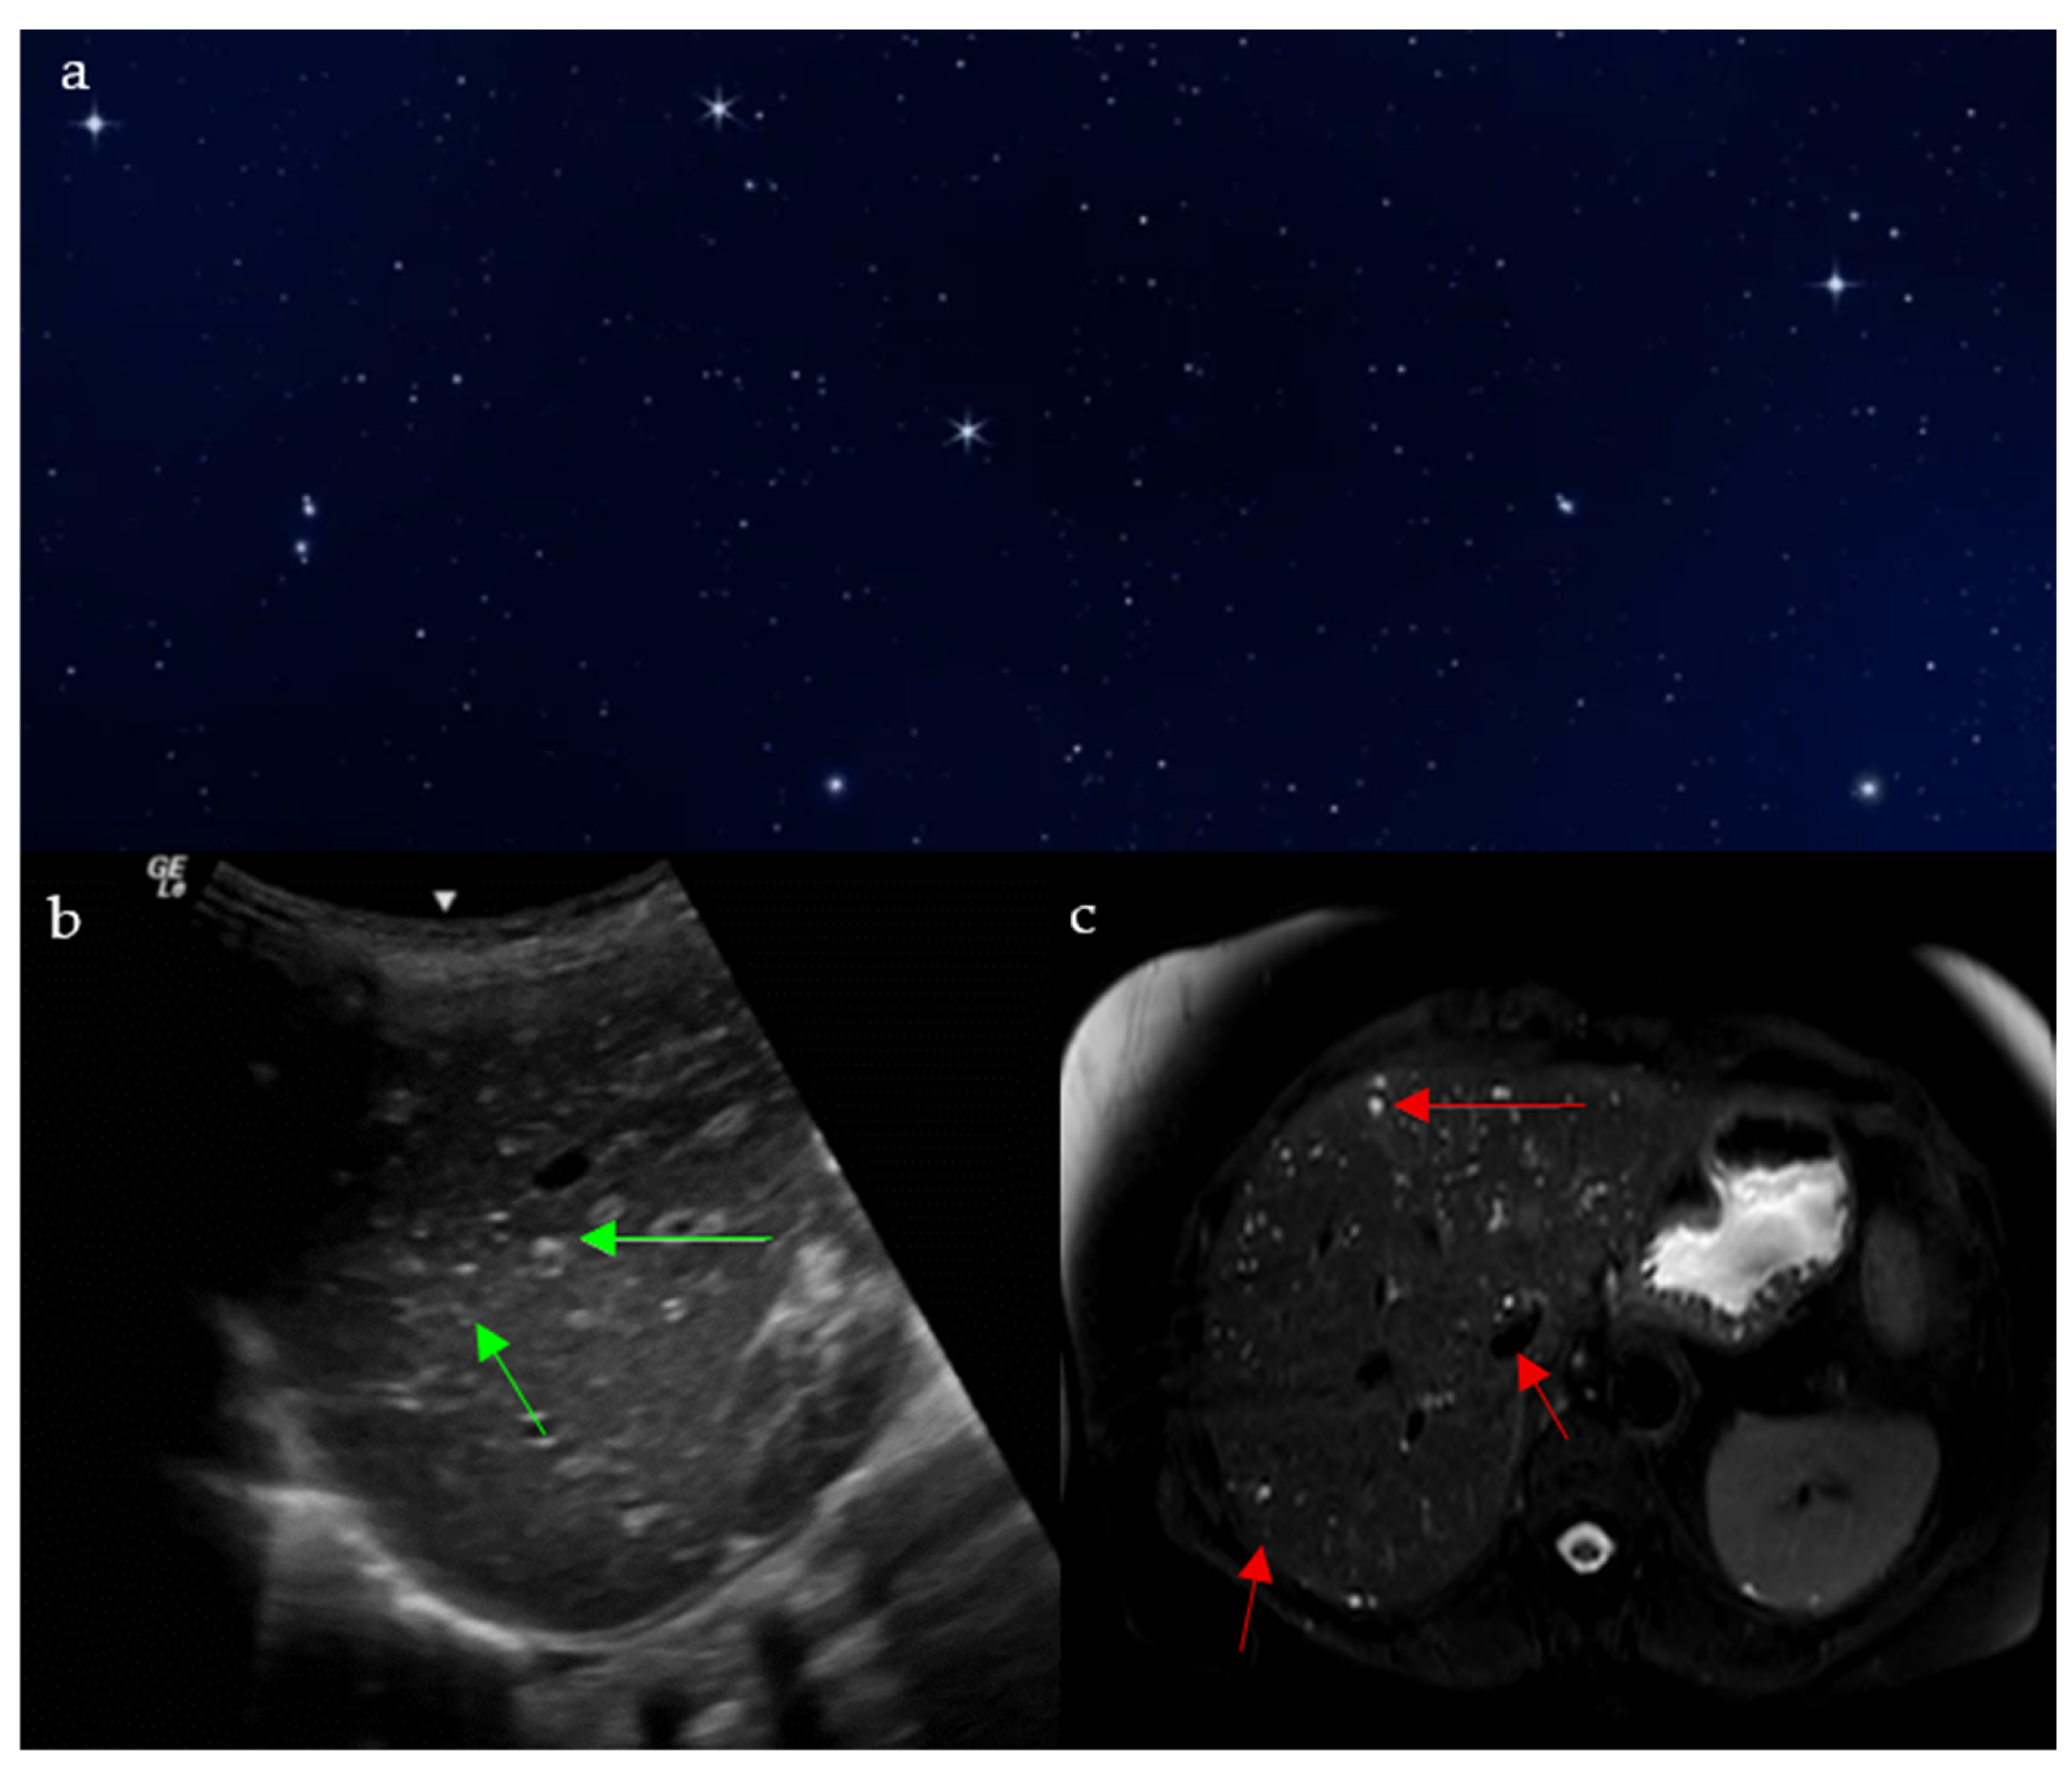

2.8. Starry Sky Appearance

2.8.1. On Ultrasound

2.8.2. On MRI